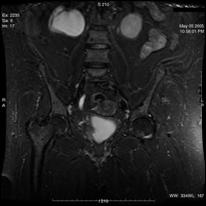

b). Neoplasm de col uterin, invaziv in vezica urinara

a. b.

a) Tumora de col uterin, invaziva in vezica urinara - pacienta s-a prezentat in anurie; b) Tumora de col uterin, operata (histerectomie totala + iradiere), recidivata, invadand vezica urinara si rectul - pacienta s-a prezentat cu hematurie